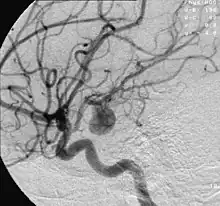

Angiography of an aneurysm in a brain artery. The aneurysm is the large bulge in the center of the image.